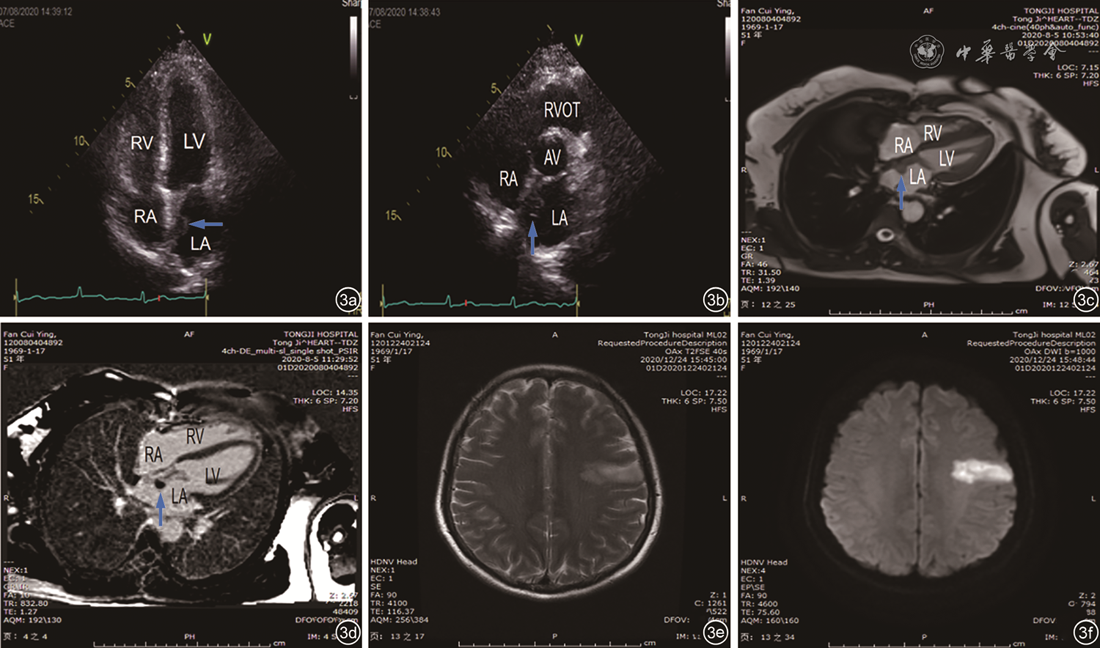

图3 左心房梭形细胞肉瘤术后复发超声心动图、心脏磁共振成像及头部磁共振图像。图a、b为常规经胸超声心动图显示左心房房间隔处复发低回声病灶(箭头所示);图c、d为心脏磁共振成像显示房间隔处异常信号影首过灌注轻度强化,延迟增强不均匀(箭头所示);图e、f为头部磁共振成像及弥散加权成像显示左侧颞叶长T2异常信号影,并且明显弥散受限注:LA为左心房;LV为左心室;RA为右心房;RV为右心室;RVOT为右心室流出道;AV为主动脉瓣